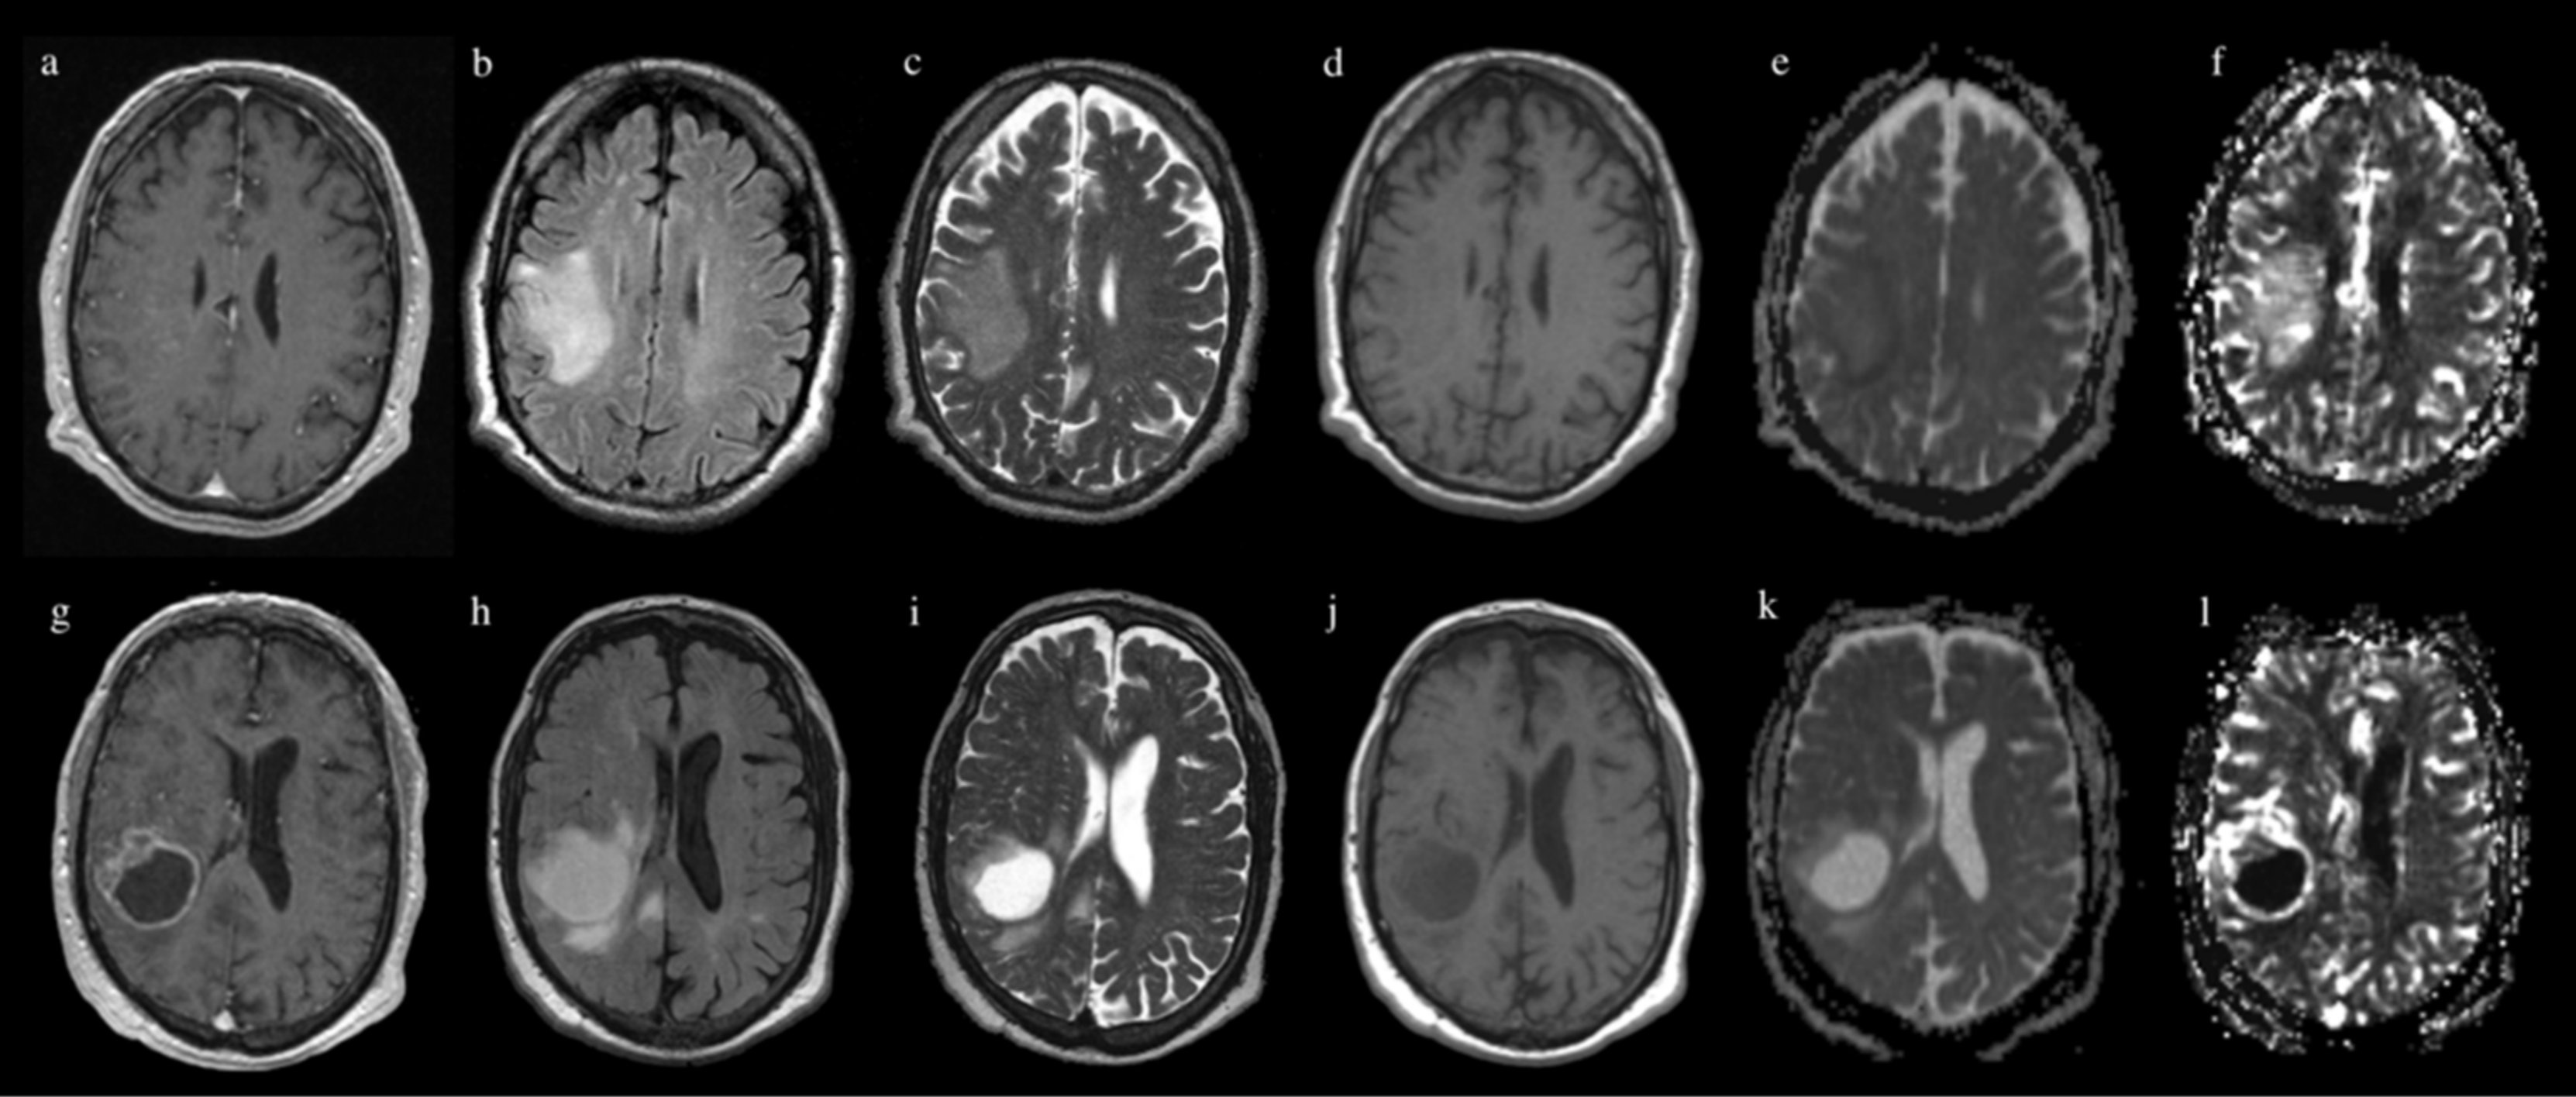

2. Materials and Methods

2.3. MR Image Acquisition

2.4. Image Processing

| ADC | 0.56 ± 0.11 | 2.53 ± 0.28 | 0.14 ± 0.07 | 0.73 ± 0.16 | 0.45 ± 0.04 |